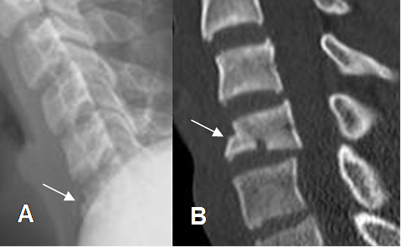

Fig 202. Fractura en cuña.

A: Rx lateral. Rectificación y pérdida den la nitidez de los contornos, en lo visualizado del cuerpo de C6.

B: TAC reconstrucción sagital. Fractura con acuñamiento anterior de la vértebra.

Fig 203. Fractura en cuña.

A: Rx lateral. Fractura en la parte anterosuperior del cuerpo.

B: TAC axial y C: TAC reconstrucción sagital. Fractura conminuta, con acuñamiento anterior de la vértebra.